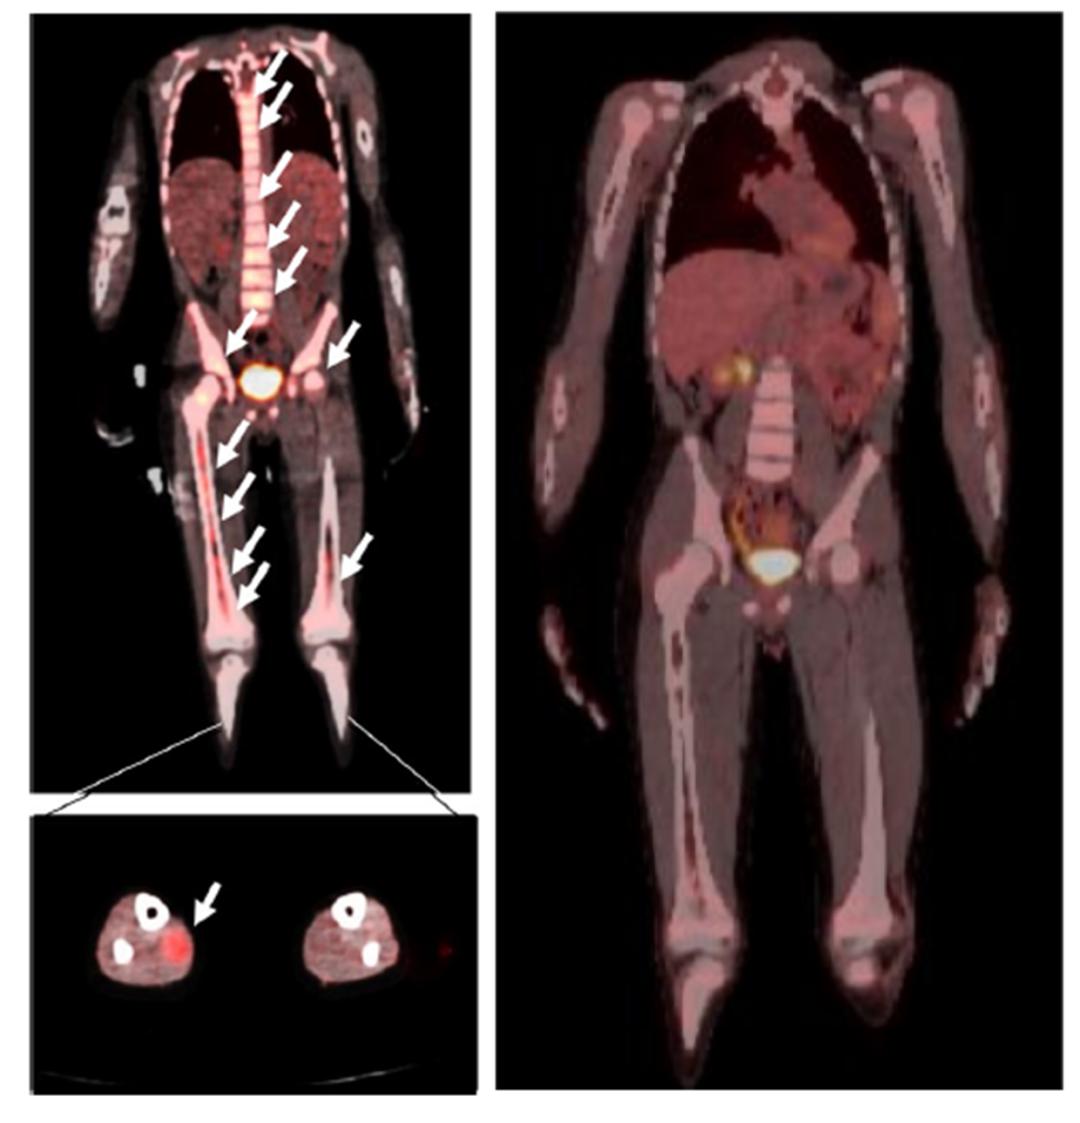

患儿CAR-T治疗前后肿瘤情况对比。

这项新研究里的这位患儿得的是骨髓转移的晚期横纹肌肉瘤,这种情况的患儿里,有一半的生存时间在一年半以下。而这位参与研究的患儿,从第一次输注CAR-T细胞算起,至今已经生存了4年多,而且至报道时,一直是无病生存。这是非常惊人的效果。

第一,这个孩子无论是腿部肌肉处的肿瘤细胞,还是骨髓中的肿瘤细胞,都表达了一种叫做HER2的特殊标记,可以作为CAR-T细胞识别的靶点。

第二,在进行CAR-T治疗前,医生给这个孩子进行了环磷酰胺和氟达拉滨的化疗预处理,去除了孩子体内的淋巴细胞,同时让孩子体内一种叫白介素15的免疫分子水平升高。这两者可以帮助CAR-T细胞扩增,使得输入的CAR-T细胞能够长时间“繁殖”,持续发挥作用。

第三,这个孩子总共接受了数十次的CAR-T治疗,疗效得到了巩固。这是一个很有意义的现象——虽然这个孩子的CAR-T治疗效果很好,但其过程并不是一帆风顺。在第一阶段CAR-T治疗获得完全缓解6个月后,肿瘤再次在骨髓中复发。

幸运的是,复发的骨髓肿瘤细胞仍然表达有HER2分子,因此医生让孩子再次接受了同样的HER2 CAR-T治疗,再次完全缓解。